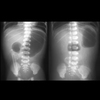

• First line = AXR: look for evidence of distended colon as unlikely to be Hirschsprung’s if no distension. May be done to diagnose intestinal obstruction and look for features of Hirschsprung-associated enterocolitis

• Rectal biopsy used to confirm diagnosis: histology shows absence of ganglionic cells